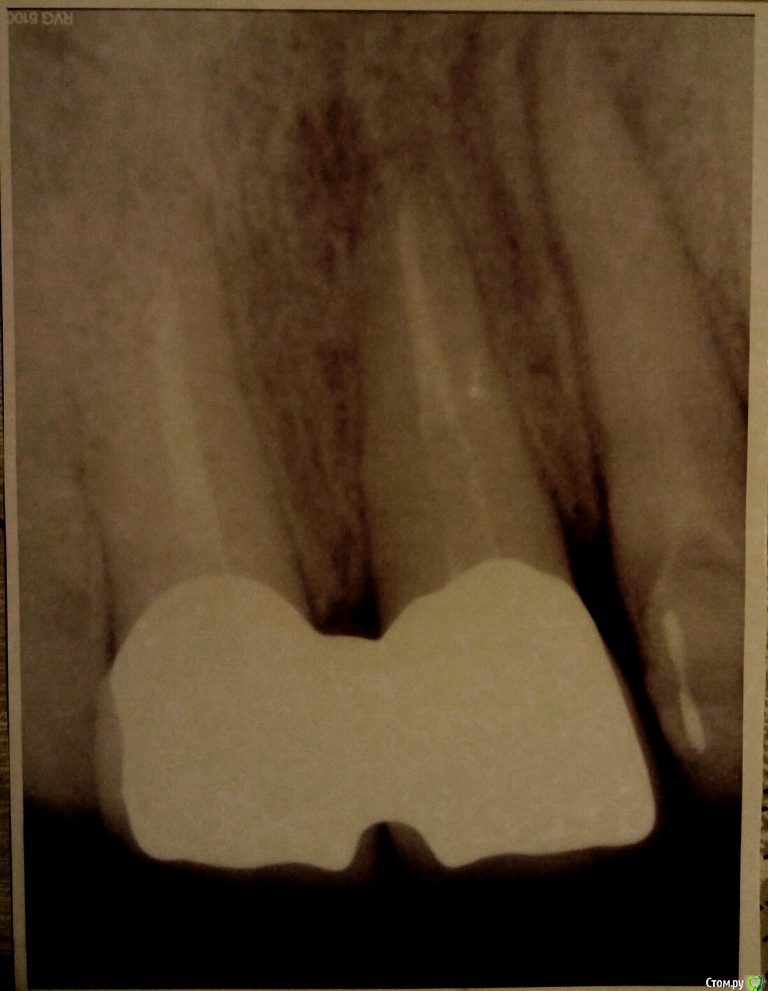

Иноземцева Опубликовано 19 декабря, 2015 Автор Поделиться Опубликовано 19 декабря, 2015 Сегодня была на консультации у другого ортопеда, сделала прицельный снимок. Он сказал,что каналы на передних единицах плохо запломбированы, плохое сцепление коронки с культей зуба (возможно она была не правильно обточена), необходимо их пролечить заново,сделать культевые вкладки, отлить новые коронки и их устанавливать.Старые коронки нельзя просто снова посадить на цемент. Но боюсь, что врач у которого я ставила коронки не пойдет на это... Т.к. он мне сказал, что могу ходить,пока коронки сами не отвалятся (не обращая внимания что появился запах и десна кровоточат), а потом он просто их снова "приклеит". Подскажите пожалуйста, как быть в данной ситуации и что я могу требовать у врача? На фото примерная хронология установления коронок. Видно ли из снимка,что тот врач сделал свою работу не качественно? Огромное спасибо всем ответившим! Ссылка на комментарий

M@estro Опубликовано 19 декабря, 2015 Поделиться Опубликовано 19 декабря, 2015 Требовать от врача никогда ничего не надо - это бесполезно и , более того, может привести к ухудшению клинической ситуации. P.s. Судя по снимку "октябрь 2014" и сравнении его со снимком "сентябрь 2014" - зубы просто уничтожены бором. Надо обратиться к квалифицированному специалисту за помощью, который проведет очный осмотр с целью оценки функциональной ценности зубов. Объективный осмотр предпочтительнее снимков в этом аспекте. 1 Ссылка на комментарий